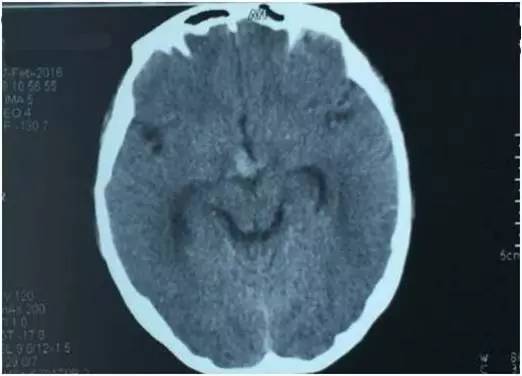

基本信息:患者女性,52岁,SAH第11天行血管内治疗。术前一般情况好,无明显阳性体征。

▼CT显示脚间池出血